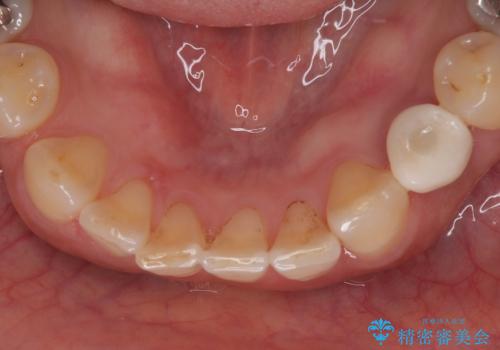

治療は計画通りに進み、約3か月で最終補綴まで完了。

見た目だけでなく、しっかり噛める機能も回復し、患者様にも大変ご満足いただけました。